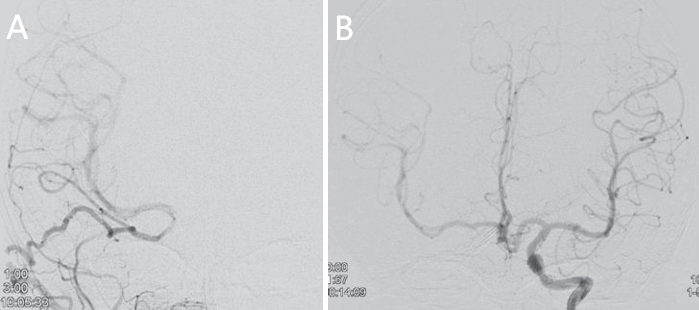

术后6个月:复查脑血管造影显示动脉瘤已经消失,令全家人都松了口气。

术后20个月:动脉瘤消失未复发。

- A,第二次手术后 6 个月内获得的前后(AP)右颈外动脉血管造影,显示颅内外血流至右侧 MCA 区域的大面积和 STA 移植物扩大。

- B,第二次手术后 6 个月左颈内动脉血管造影显示,与第二次手术前相比,通过前交通动脉的右侧 MCA 区域的侧支血流减少。